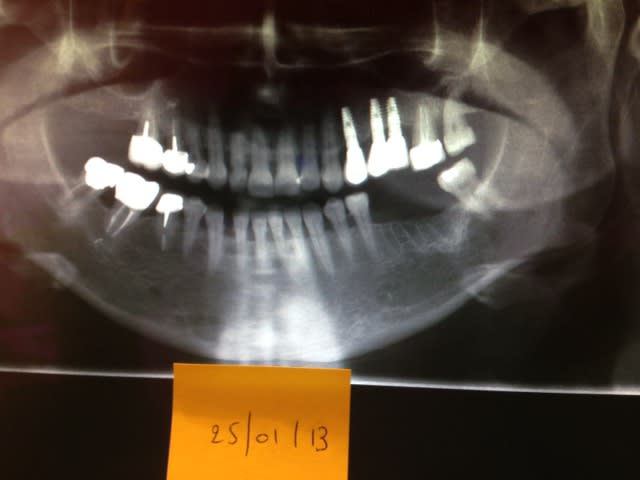

je sollicite votre avis pour une image que je trouve radio claire secteur 3 , je me demande si le jeu de contraste des radios créent cette illusion ou pas.

Mme N... , 54 ans, opérée d'un cancer du sein en octobre 2011 avec rayons et chimio car il y a eu extension aux os des jambes.

Elle est actuellemnt sous clastoban (biphosphonate) en comprimé depuis juin 2012 avec 2 injections du même produit , en novembre 2011 pour la 1ere , et en mars 2012 pour la 2é.

- sept 2011 pose de 3 implants secteur 2

- janv 2012 extraction et urgence de 37/36

- Le projet d'implants secteur 3 est reporté évidemment.

l'image radioclaire semble présente sur la vieille pano (on voit pas très bien.)

Est-ce de l'osteo-chimio-nécrose due aux extractions ou est-ce une lésion tumorale comme elle a pu avoir aux jambes ?

je pencherais pour une lésion préop.

Après traitement IV avec bisphosphonates, pas d implanto

Jamais ni tout de suite ni un peu plus tard ni même très tard

Les concentrations osseuses atteintes par les traitments IV sont tjs trop hautes pour permettre la pose d implants